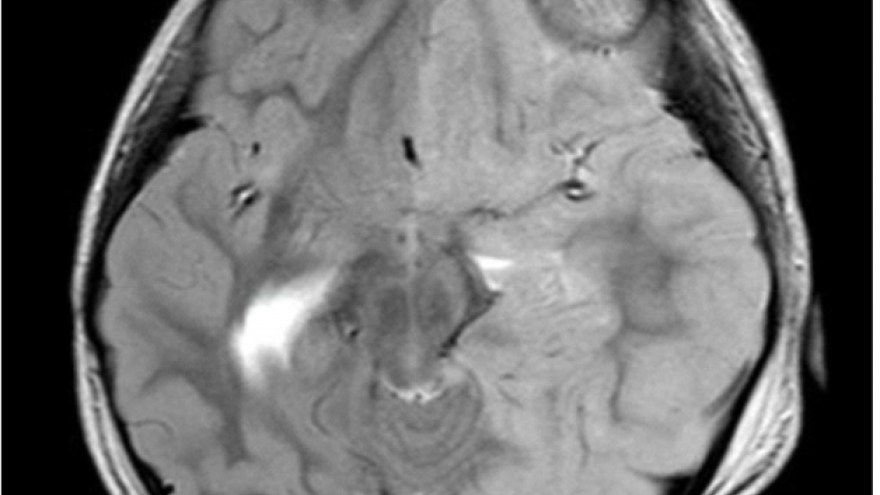

VOV.VN - Bệnh viện Chợ Rẫy vừa tiếp nhận 2 nữ bệnh nhân bị tai biến do tiêm filler trong một khách sạn tại Tây Ninh. Đáng nói là, 1 nạn nhân còn bị "lột" sạch tài sản trên người.